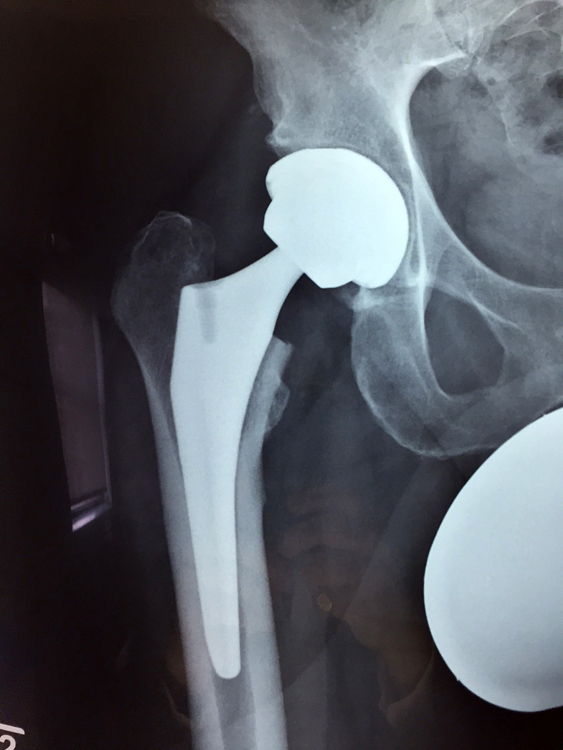

For anyone concerned about the size of a hip replacement wound, and how quickly it heals, I have

been amazed at the pace of the healing process, shown in the adjacent pictures, with the left one being the bruising after 8 days, and the right one showing the wound (much closer with most of the bruising having gone) after 16 days. The wound itself is only about four inches long!